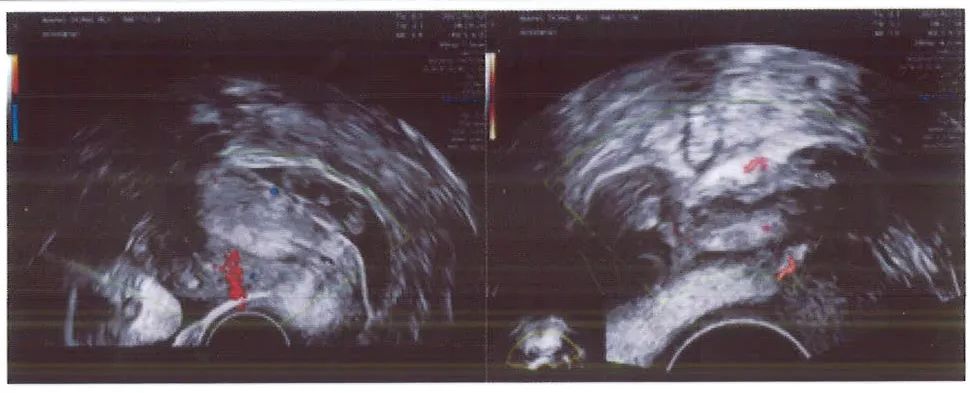

术前超声检查

当日夜间患者再次出现 阵发性右下腹痛 ,次日超声检查发现包块明显增大,考虑到患者病情较前加重,如果继续保守治疗的话,则有输卵管破裂、大出血、休克的风险,应 及时进行手术治疗 。